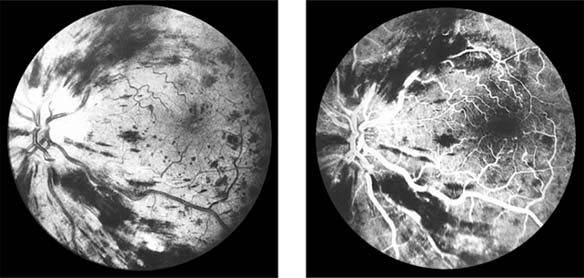

Central Retinal Vein Occlusion (new window  Figure 15-7)

Figure 15-7

Figure 15-7: Central retinal vein occlusion. Left: Photograph shows linear hemorrhages in the nerve fiber layer and punctate hemorrhages in the deeper retinal layers. Right: Fluorescein angiogram shows dilation of the veins.

Fundus examination shows dilated tortuous veins with retinal and macular edema, hemorrhages all over the posterior pole, and cotton-wool spots. The arterioles are usually attenuated, indicating generalized microvascular disease.

The prognosis for vision is poor. Fluorescein angiography demonstrates two types of response: a nonischemic type, with dilation of retinal vessels and edema; and an ischemic type, with large areas of capillary nonperfusion or evidence of retinal or anterior segment neovascularization. In 93% of ischemic and 50% of nonischemic central retinal vein occlusions, the ultimate visual acuity is less than 20/200.